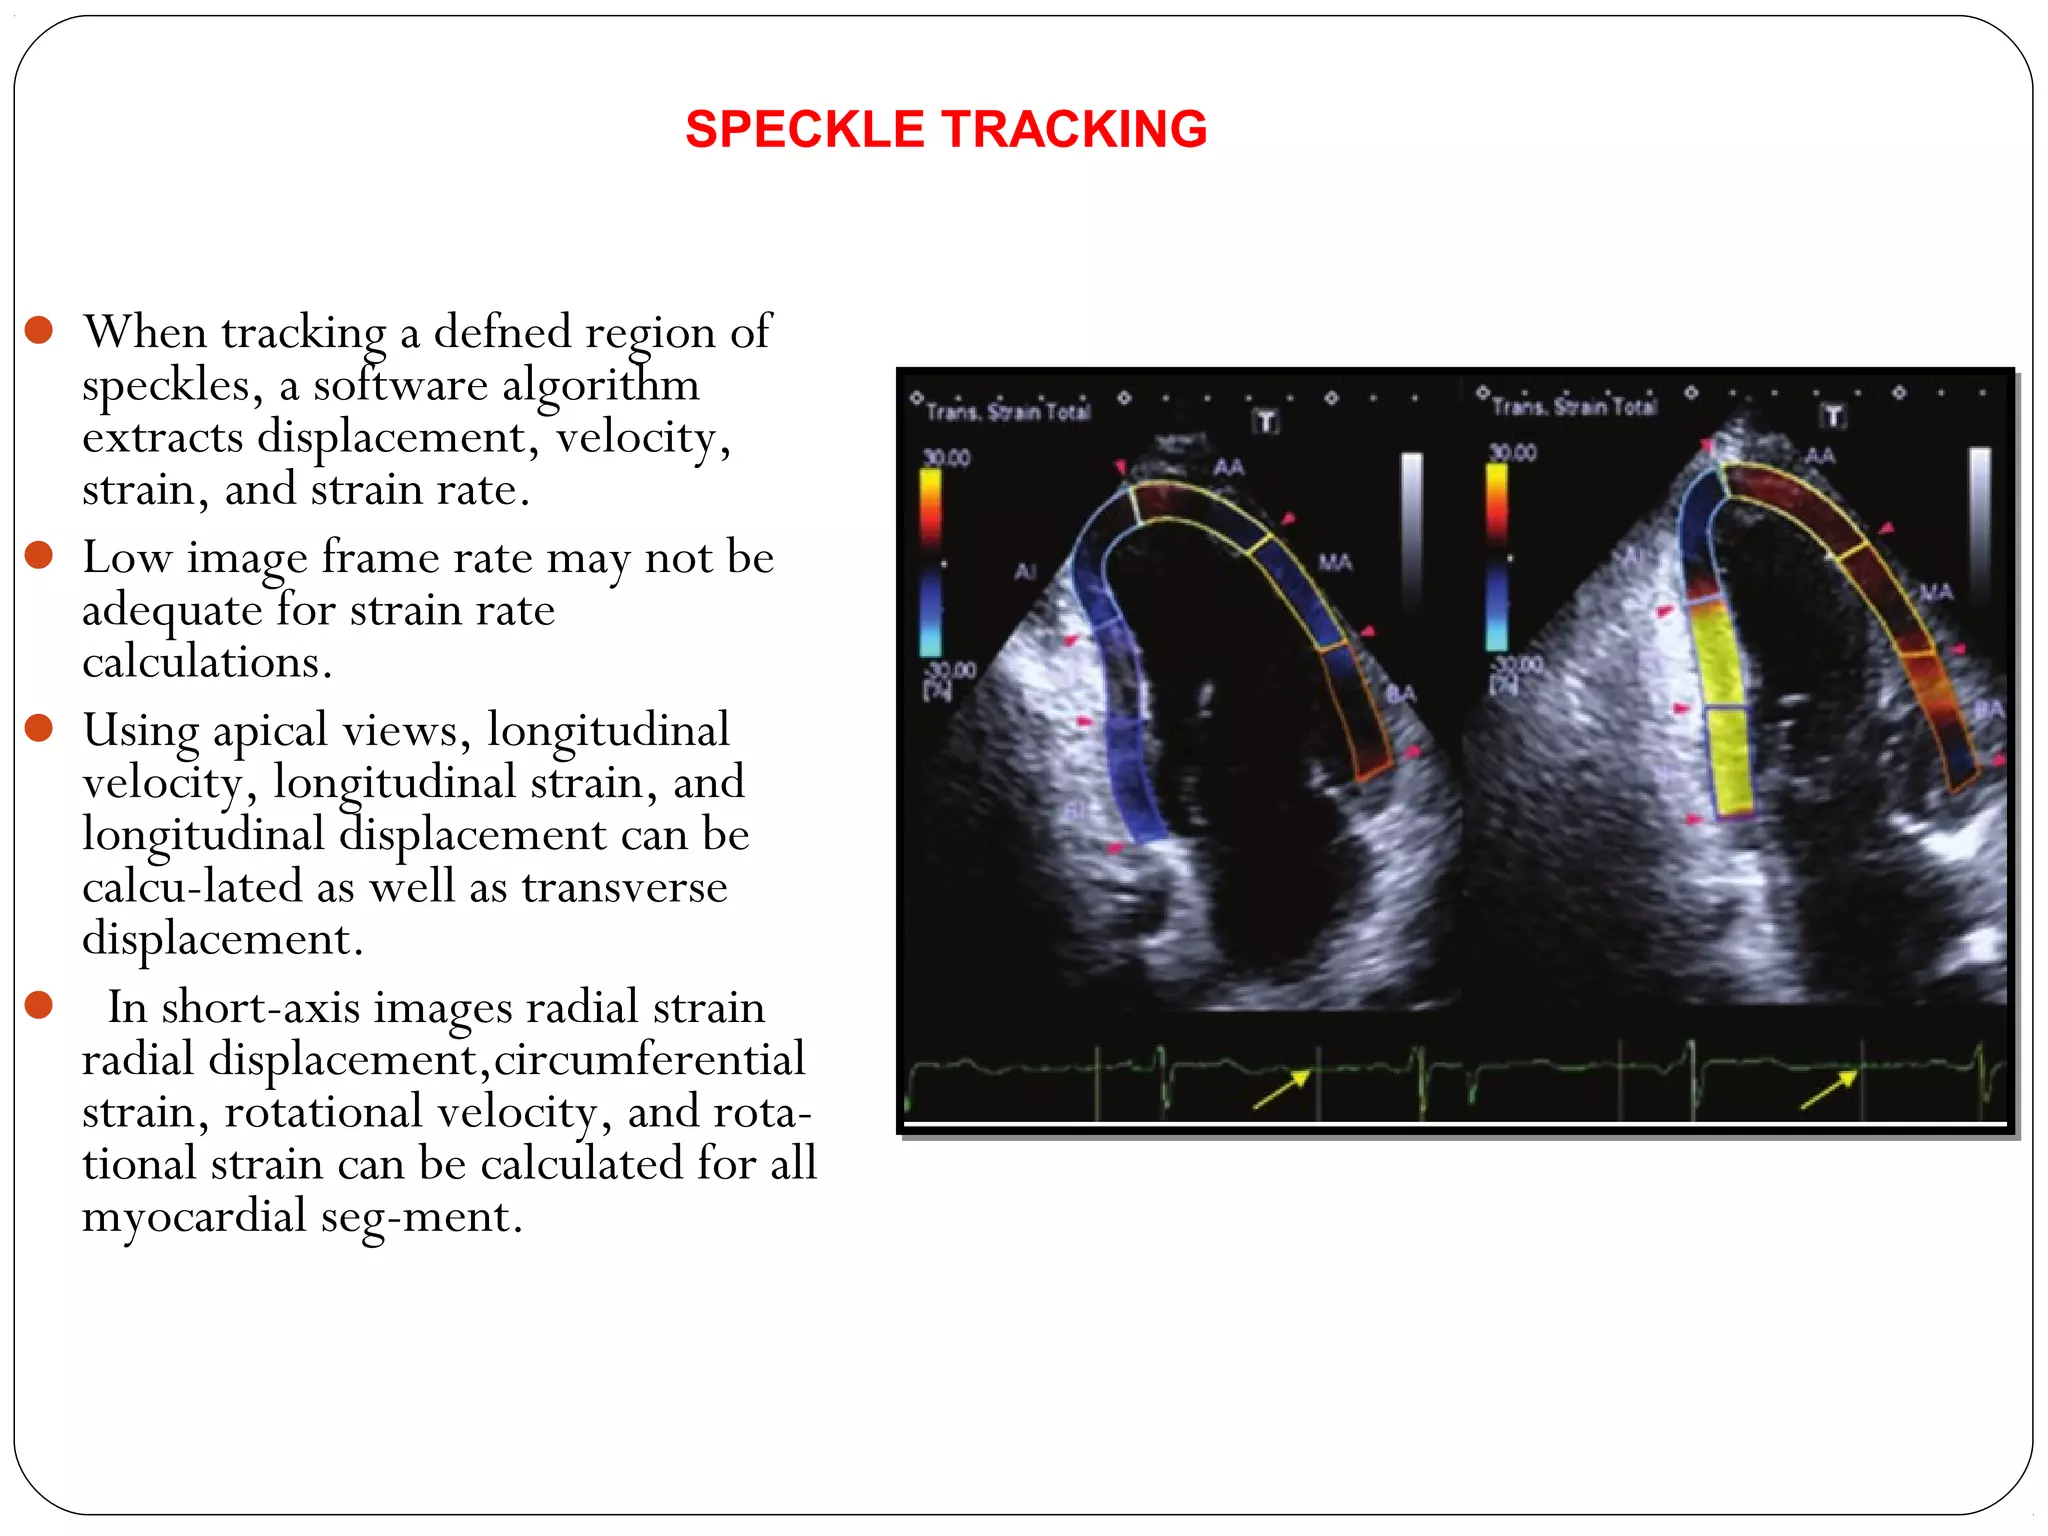

 When tracking a defned region of

speckles, a software algorithm

extracts displacement, velocity,

strain, and strain rate.

 Low image frame rate may not be

adequate for strain rate

calculations.

 Using apical views, longitudinal

velocity, longitudinal strain, and

longitudinal displacement can be

calcu-lated as well as transverse

displacement.

 In short-axis images radial strain

radial displacement,circumferential

strain, rotational velocity, and rota-

tional strain can be calculated for all

myocardial seg-ment.